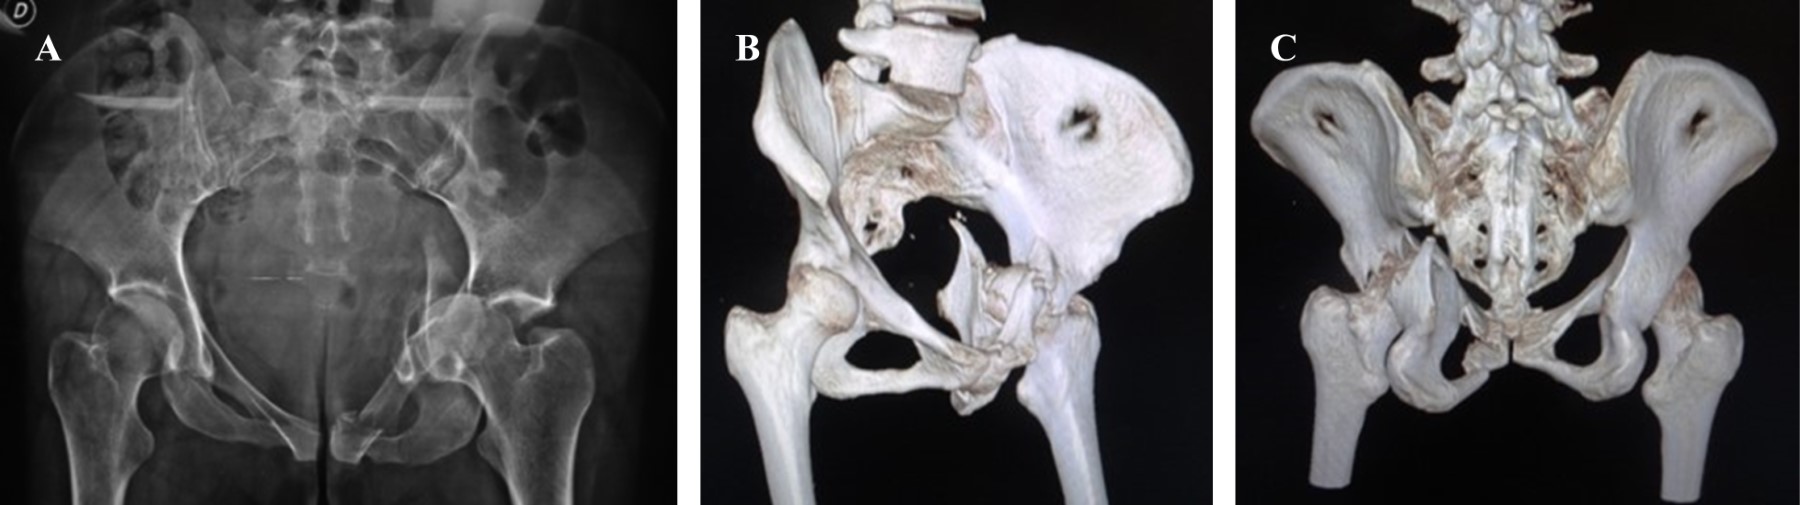

Indicaciones. Fracturas de los elementos anteriores: pared anterior, columna anterior, fractura de columna y pared anterior, fracturas transversas o en "T" con afección mayor a la columna anterior, fractura de ambas columnas, fractura anterior y posterior hemitransversa o fracturas atípicas (Figura 1).5,6

Contraindicaciones. Fracturas de los elementos posteriores: pared o columna posterior, fractura transversa y pared posterior, fracturas transversas con principal desplazamiento en columna posterior.7

Planificación preoperatoria. Las fracturas acetabulares desplazadas son, por lo general, resultado de mecanismos de alta energía; por tal razón, la condición general del paciente debe estudiarse de acuerdo con los protocolos de trauma establecidos y, una vez estabilizado, llevar a cabo un plan de tratamiento que incluye identificación y clasificación precisa de la lesión pélvica mediante estudios de imagen que deben incluir serie pélvica radiográfica (anteroposterior de pelvis, oblicua alar, oblicua obturatriz proyección de entrada y de salida de pelvis) y tomografía axial. Una vez clasificada la lesión deberá establecerse un plan de tratamiento que incluya la selección del abordaje quirúrgico y la secuencia de reducción de las fracturas presentes.8,9,10

Figura 1